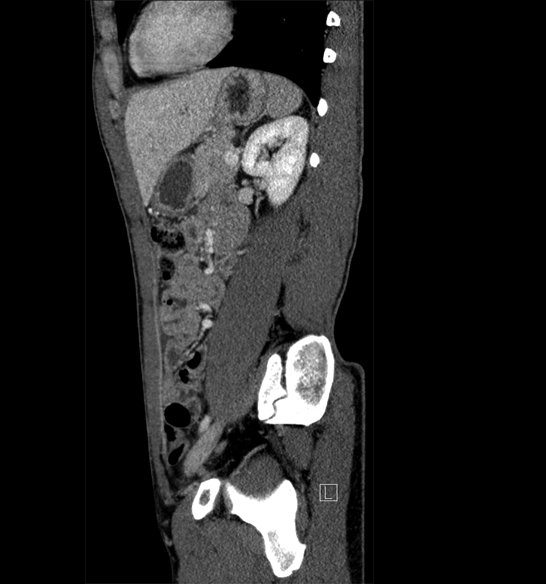

Body

Covers abdominal CT anatomy.